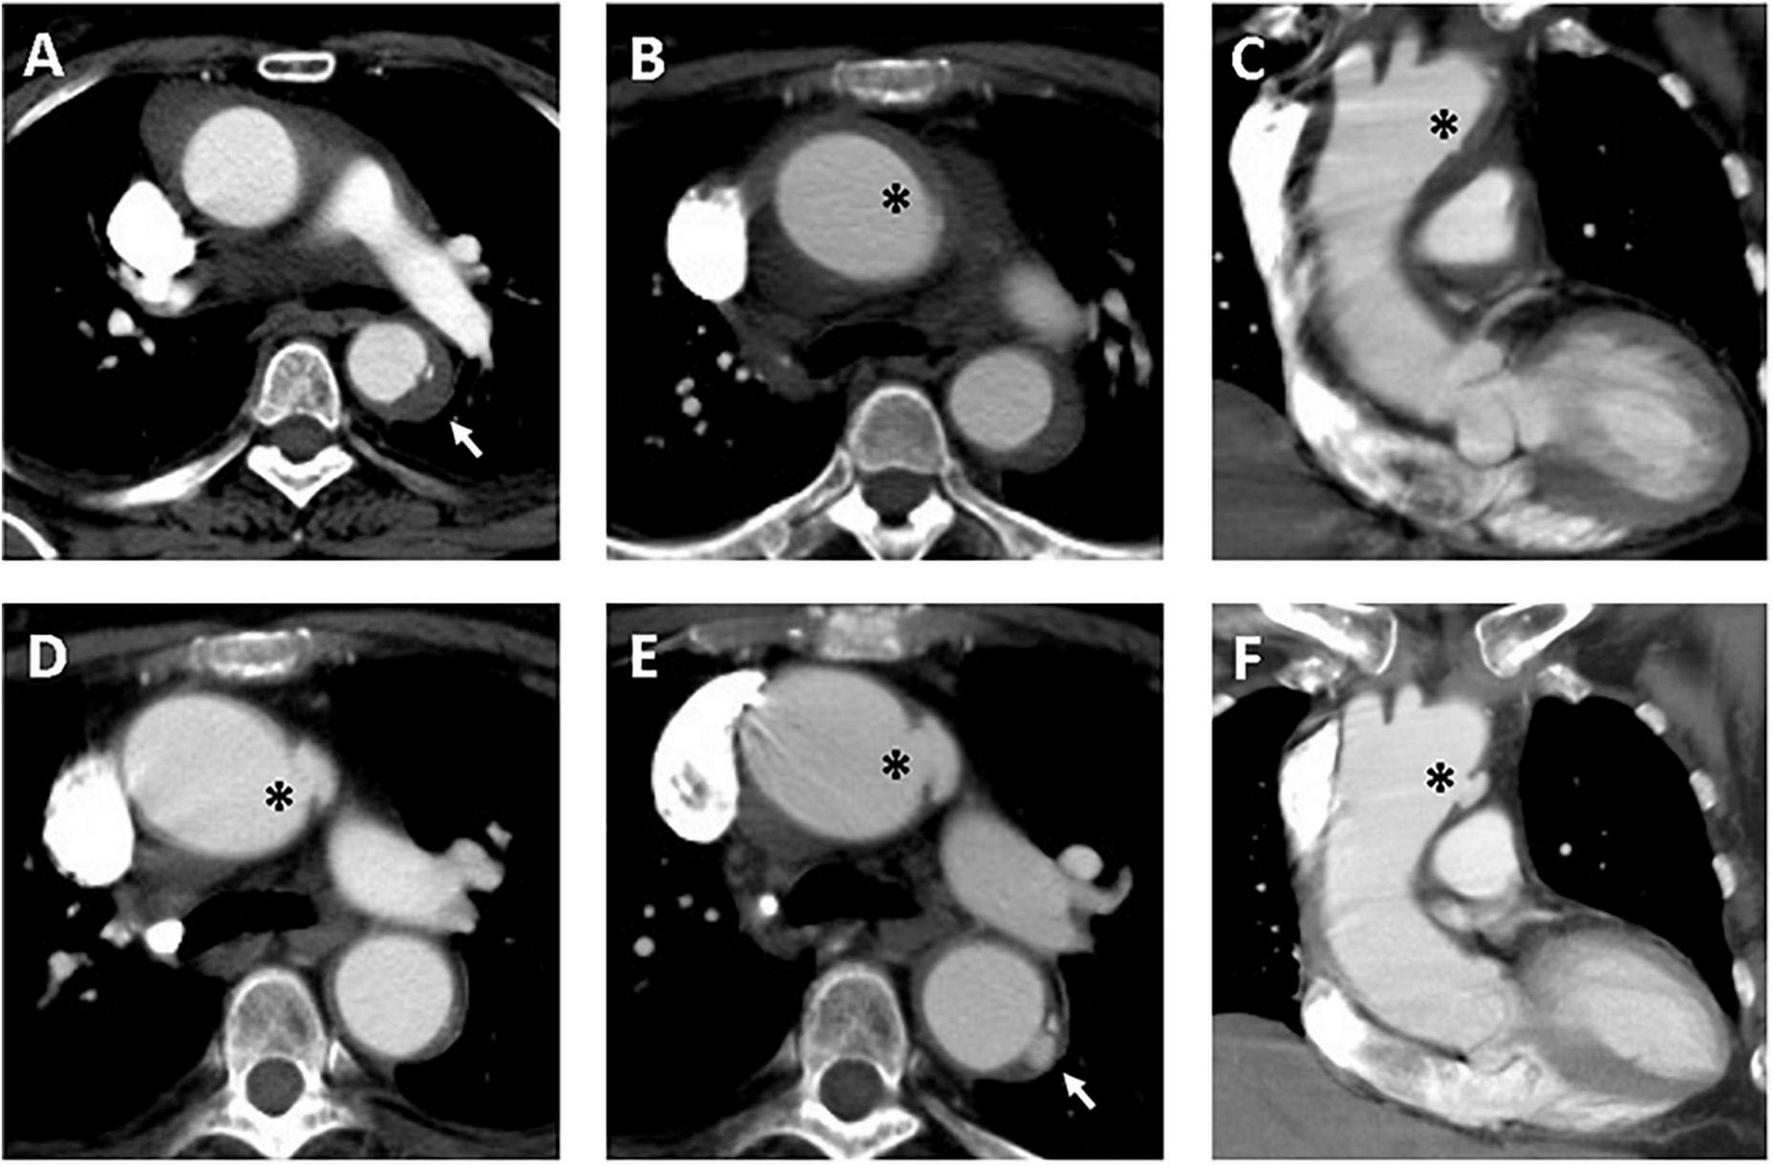

FIGURE 3

Serial CT scans showed progression of PAU and ULP in a 69-year-old woman with TAIMH. Contrast-enhanced CT scan showed TAIMH with PAU (arrow) in the proximal descending aorta (A) and ULP (asterisk) in the proximal aortic arch (B,C). Three months later, the follow-up CT scan showed enlarged ULP (D, asterisk). The PAU (arrow) in the proximal descending aorta and ULP (asterisk) in the proximal aortic arch were slowly progressed in overall size on 14-month follow-up CT scan (E,F). The patient received medical treatment alone and was still alive.